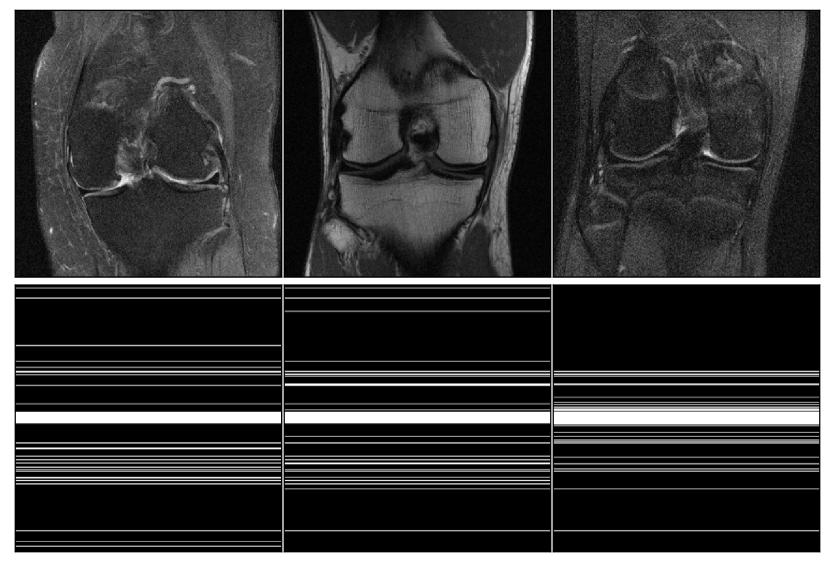

Refer to caption

(a) 8×\times acceleration masks (second row) predicted by MNet for different training slices (first row): Base low-frequency information contains the central 8 rows, and the sampling budget for high-frequency information is 32 rows.

(b) 4×\times acceleration masks (second row) predicted by MNet for different training slices (first row). Base low-frequency information contains the central 16 rows, and the sampling budget for high-frequency information is 64 rows.

Figure 3: Adaptively predicted masks from MNet for slice examples in the single-coil FastMRI knee dataset.

In Figure 3, we visualize the adaptive masks output from the adaptive sampler MNet trained by Algorithm 2. Knee images in Figure 3 are the ground truth images. The MNet sampler sees the low-frequency information collected in k𝑘k-space and outputs the corresponding full subsampling patterns for sampling high-frequency information in a single pass, which are shown for each image and are object-adaptive.